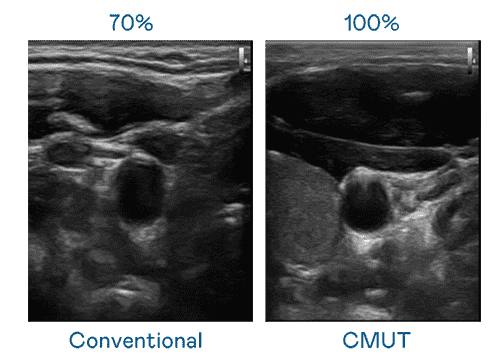

CMUT 技术是一种用电容式微机电元件来产生超音波讯号的技术。。。与传统 PZT 压电式技术相比,,CMUT 频宽增加 30%,,,,更宽频的超音波讯号让影像解析度大幅提升,,是实现高影像品质医疗超音波扫描、、、、促进精准医疗发展的关键技术。。

大频宽带来超清晰影像

超音波影像的解析度高低,,,首先取决于探头能发出的讯号频宽。。财神娱乐 CMUT 可提供高清晰的超音波讯号,,,提供高频宽、、、高灵敏度、、影像纹理细节更高的超音波影像,,协助医护人员缩短影像判读时间及利用精准的医疗影像进行诊断。。。。